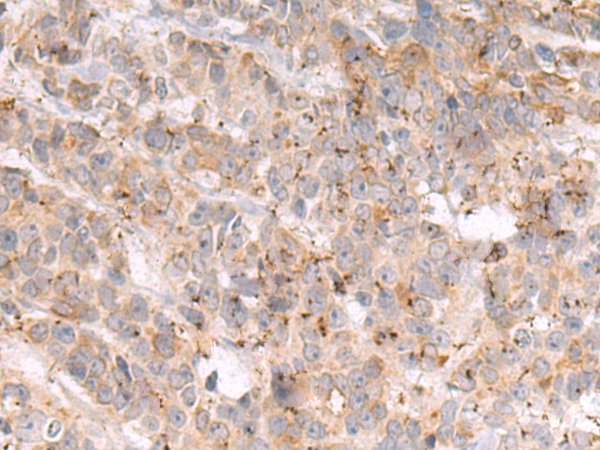

分类: 科研抗体货号: P10600别名: FAKTS; URLC9; hFLEG1应用: IHC反应种属: Human